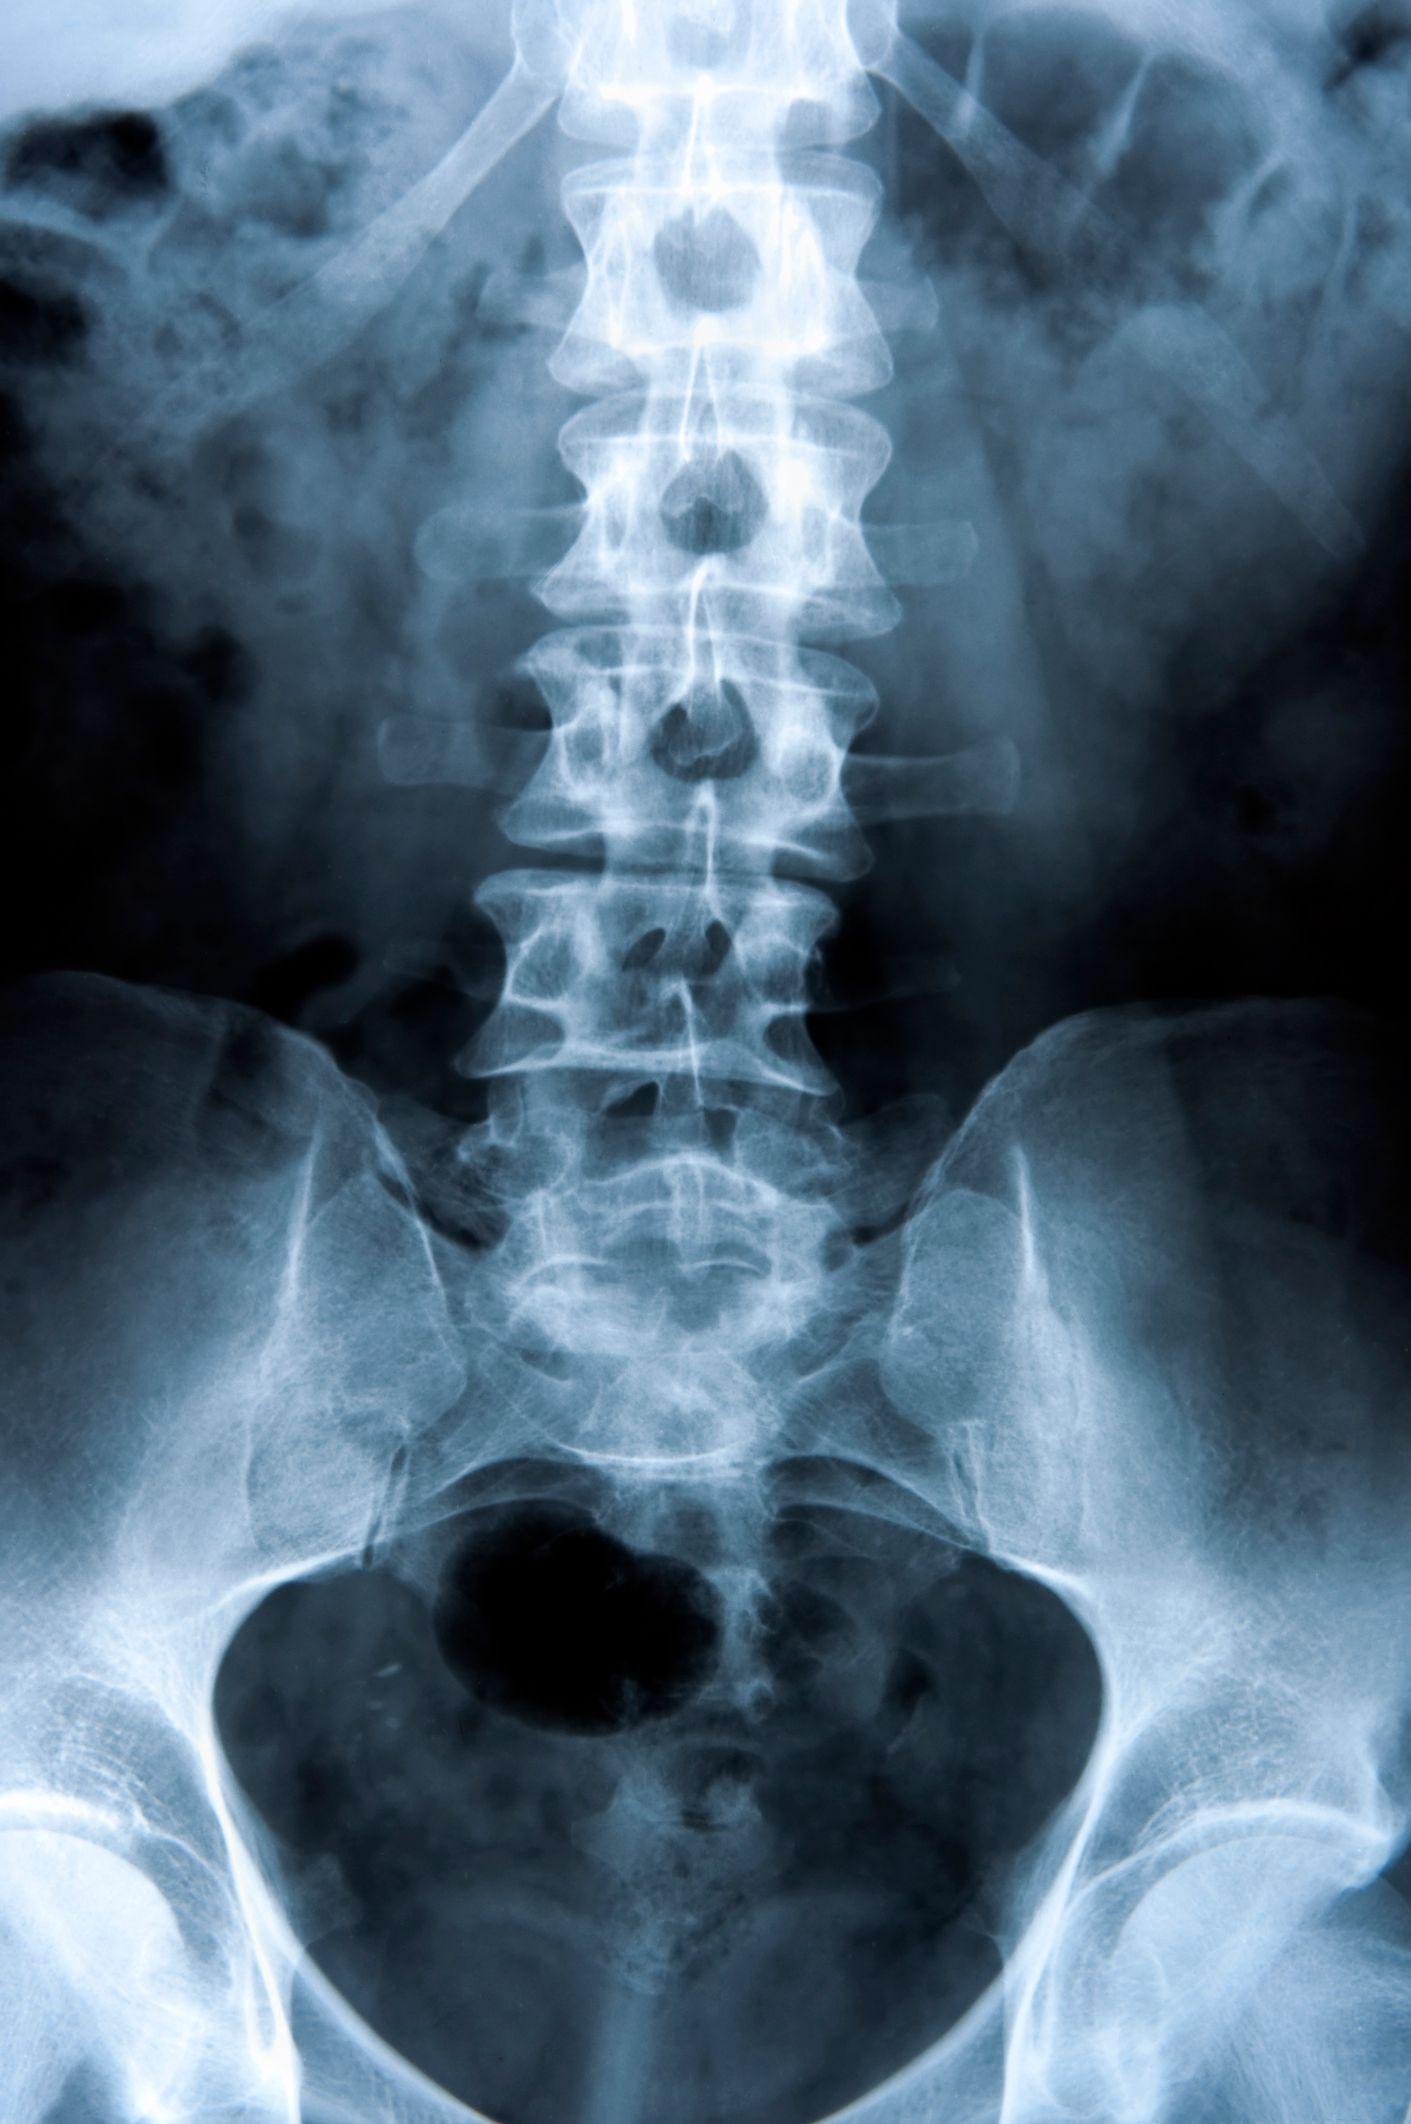

Understanding Scoliosis: Causes, Diagnosis, and Treatment